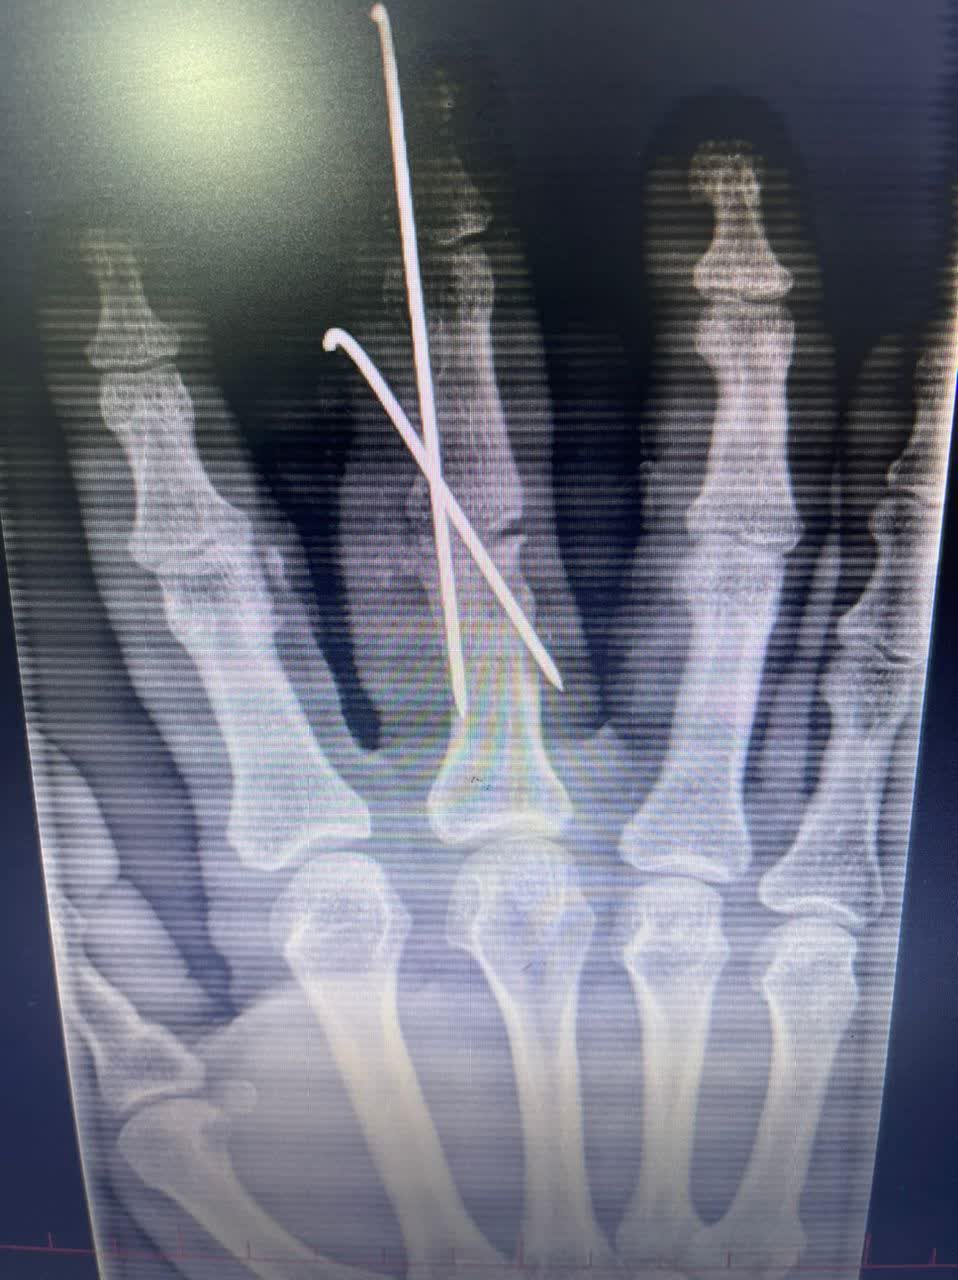

بنا به گزارش روابط عمومی بیمارستان قمربنی هاشم (ع) جوین:انجام عمل سنگین جراحی تعویض مفصل لگن (THA) در بیمار ،خانمی 65 ساله از اهالی شهرستان جوین به دنبال شکستگی گردن استخوان ران و عمل جراحی استئوتومی اصلاحی انگشت در بیمار ،آقایی 33 ساله از اهالی شهرستان جوین به دنبال آسیب قدیمی ، جهت اصلاح راستای انگشت در بیمارستان قمربنی هاشم (ع) جوین انجام شد.

گرافی قبل از جراحی                                                    گرافی پس از جراحی

بعد از عمل